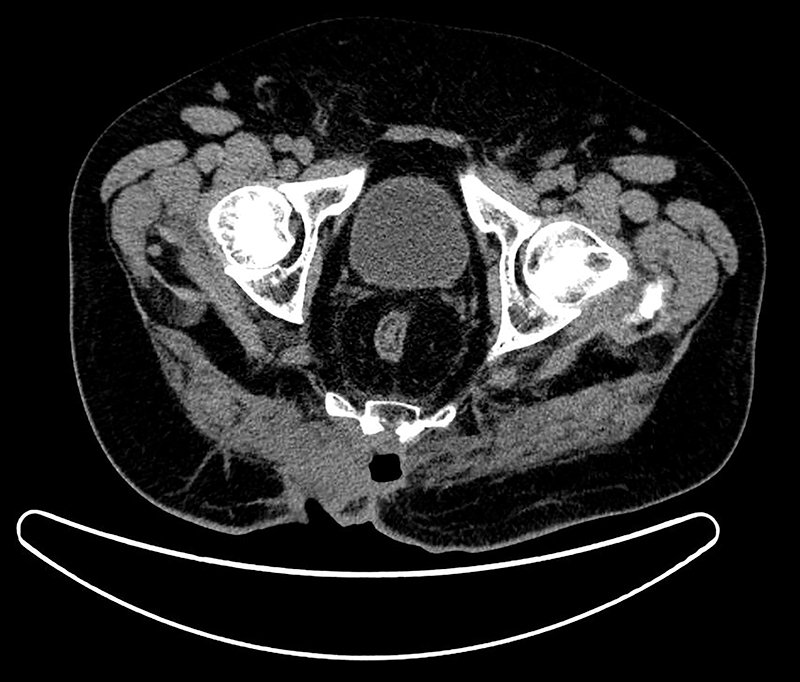

Figura 3: TAC pélvico con contraste IV como estadiaje de afectación local. Se aprecia sobreinfección de tumoración con burbuja de gas